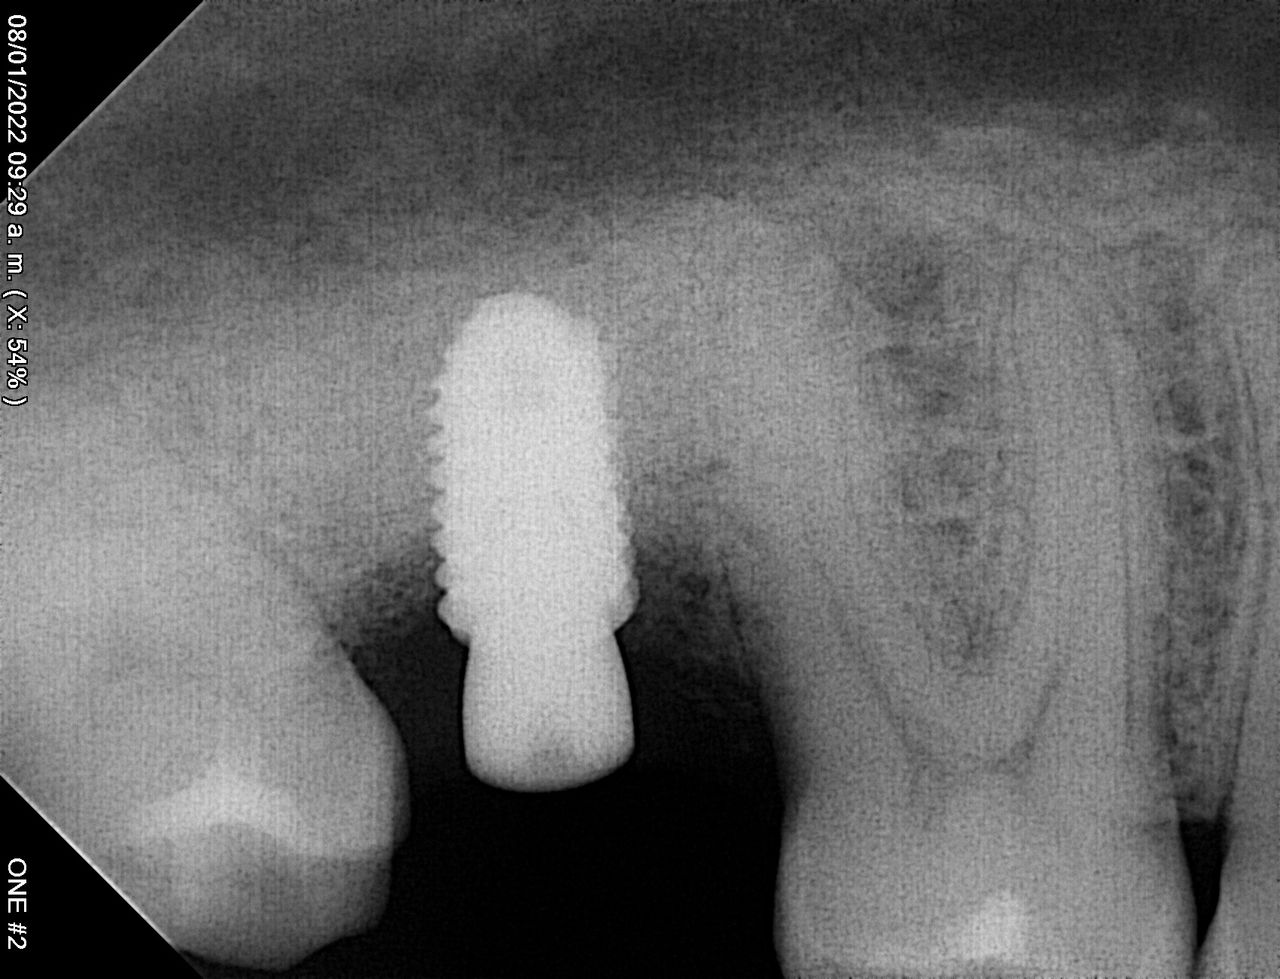

En la primera consulta se elabora un expediente clínico personalizado, respaldado por radiografías digitales y fotografías intraorales de alta precisión.

Diagnóstico por imagen

Duda sobre Parestesia

Desde hace varios años tengo una parestesia del labio inferior producida por una infección por una extracción. Me realizaron otra extracción que volvió a infectarse y la parestesia está empeorando, que debo hacer?

Buen día!

Le recomendamos realizar un estudio mas extenso llamado cone beam para ver el grado de afectación, le sugerimos acudir a una consulta para valorar su caso. Quedamos a sus órdenes.